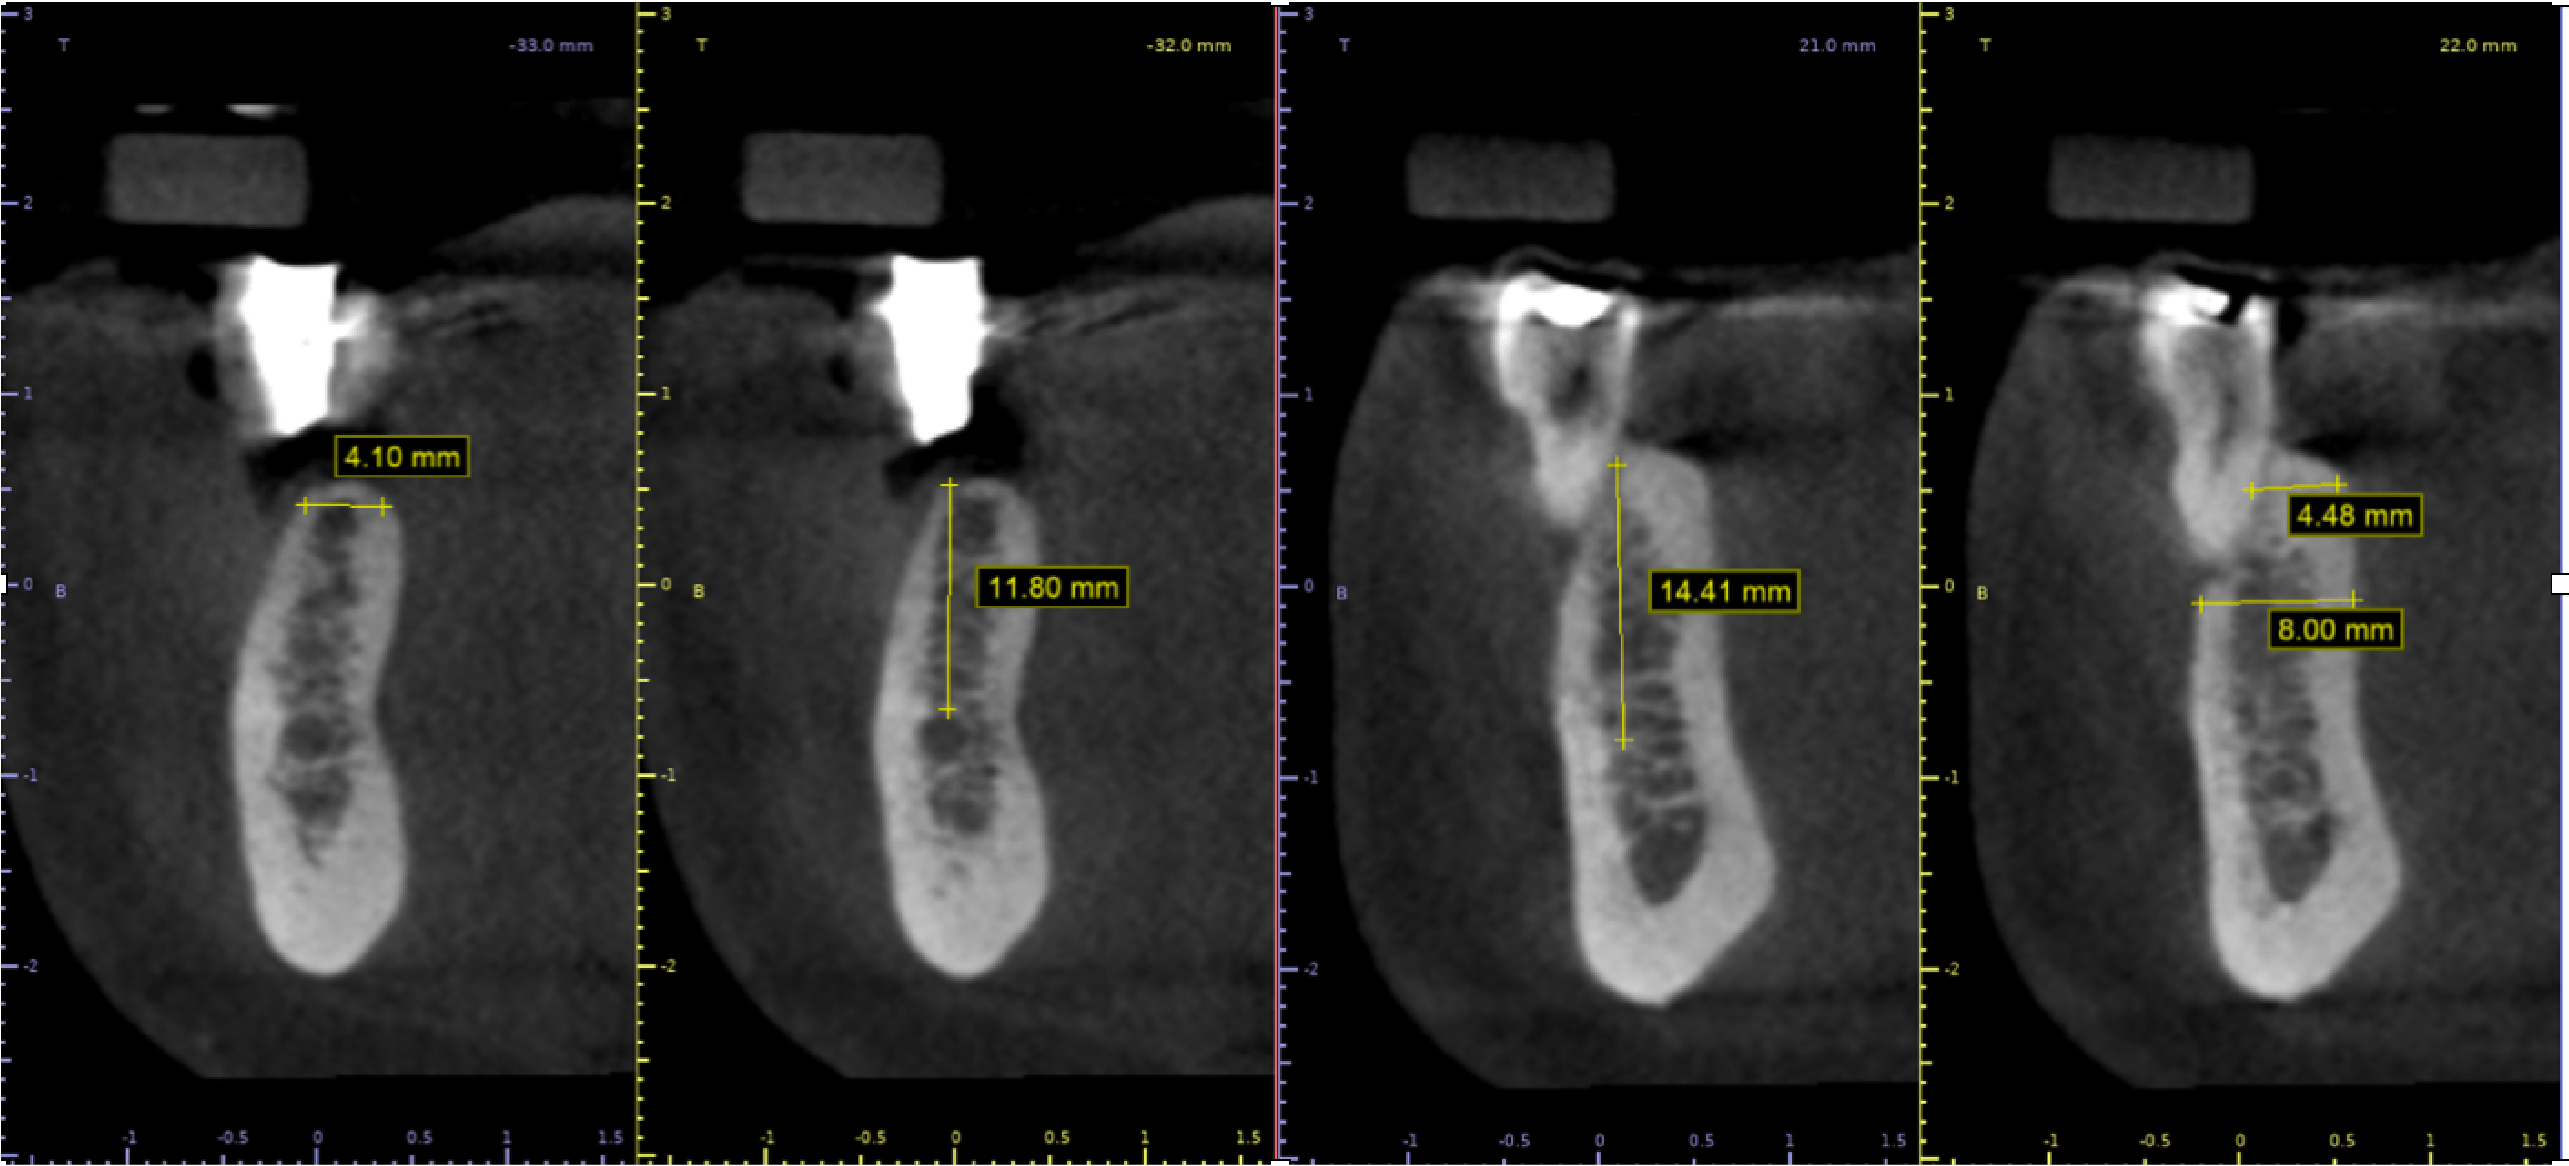

Una vez realizada la valoración completa se le indicó a la paciente la extracción de los órganos dentales “35” y “47” y la colocación de implantes en zonas de “35, 36, 46 y 47”.

Al observar los cortes tomográficos se plantea como primer paso la regeneración ósea guiada (ROG) de la zona en donde se colocarán los implantes de las piezas “35” y “36” debido al defecto tipo 3 de Seibert (Vertical y horizontal) del reborde alveolar. (Fig.5).

Fig. 5